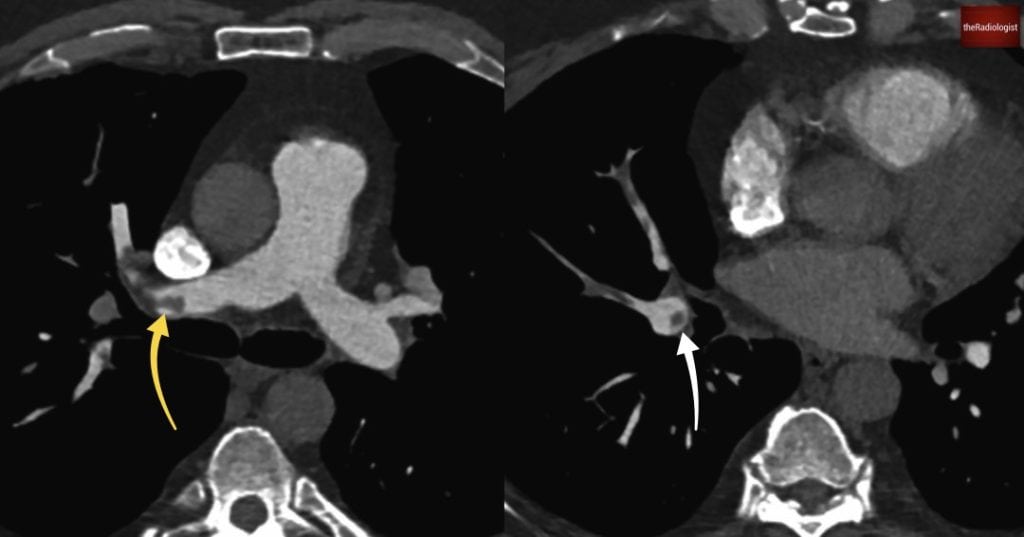

Now let’s look at the scan findings. If we follow the pulmonary arteries in this case, we’ll see that there are filling defects within the right main pulmonary artery. This extends into the right upper lobe pulmonary artery. This extends into all three right sided lobes, and we can see in some areas we have our polo sign, where we have a filling defect and contrast around this. Polo refers to the mint not the horse game (other mints are also available) and this sign suggests acute pulmonary emboli.

We can see in our case there are filling defects within the pulmonary arteries. On the left image there is a filling defect within the right main pulmonary artery (yellow arrow). Going into the right lower lobe on the right hand image we can see a ‘polo sign’ (white arrow) suggesting the pulmonary emboli are acute.